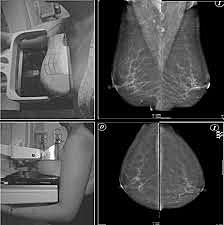

-Albert Salomon realizo la primera descripción de un estudio de mama mediante rayos X.

• Gershon – Cohen y Strickler

Gershon – Cohen y Strickler

Estudiaron diferentes formas de la mama normal, realizando comparativos con preparaciones histológicas.

• Charles Gros

Charles Gros

Desarrolla el primer mastógrafo, el cual determinaba las diferencias entre lesiones malignas y malignas mediante imagen.

-Dr. Robert L. Egan describe una técnica revolucionaria en aquella época para el estudio de la mama. Estudia 1000 casos, y en 1962 publica 53 cánceres asintomáticos (ocultos).

• BIRADS

BIRADS

Surge la terminología del sistema BIRADS por el Colegio Americano de Radiología para la interpretación de mastografías.